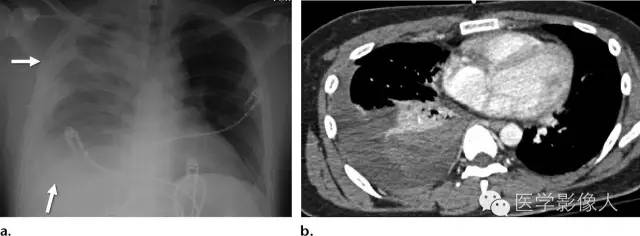

放射科医生需要注意的胸廓出口手术的几个重要潜在的短期并发症。考虑到胸廓出口受限的空间和可能需要的血管松解术,在手术后,非预期的血管损伤可能导致锁骨上区域血肿。如果还有突破顶胸膜表面或者连续性出血,可能会导致血胸。在胸廓出口减压术同侧迅速扩大的胸腔积液应考虑到血胸,CT可进一步明确,且可能需要手术引流(图11)。同样地,少量气胸是胸廓出口减压术后预期表现,正在扩大的气胸或产生张力性气胸通常需要临床立刻高度重视。

图11右侧锁骨周围胸廓出口减压手术后血胸患者,发生颈部肿胀和呼吸困难8天。 医学百科网 | YxBaike.Com

(a)胸片显示了右侧壁和肺底(箭)胸腔积液。这种新发的和相对比较迅速的胸腔积液的是令人担忧的血胸。(b)CT图像显示在右侧胸膜腔内高密度病变,与含血液成分相一致。病人随后进行了血胸引流手术。 医学百科网 | YxBaike.Com